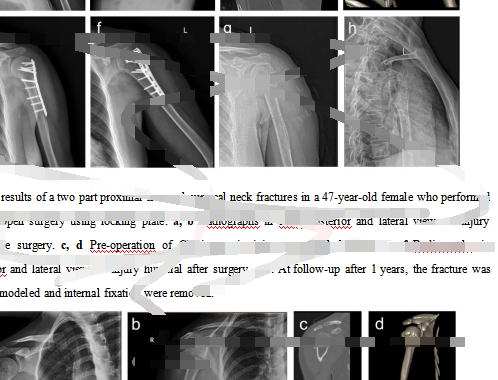

在另一家“論文工廠(chǎng)”,當記者表示著(zhù)急想發(fā)醫學(xué)方面頂級期刊,對方推薦給記者一篇已基本寫(xiě)好的頸部骨科研究英文論文,并發(fā)來(lái)部分內容供記者審核評閱,總“標價(jià)”3.75萬(wàn)元。

“論文工廠(chǎng)”發(fā)給記者的一篇已基本寫(xiě)好的頸部骨科研究英文論文的部分內容